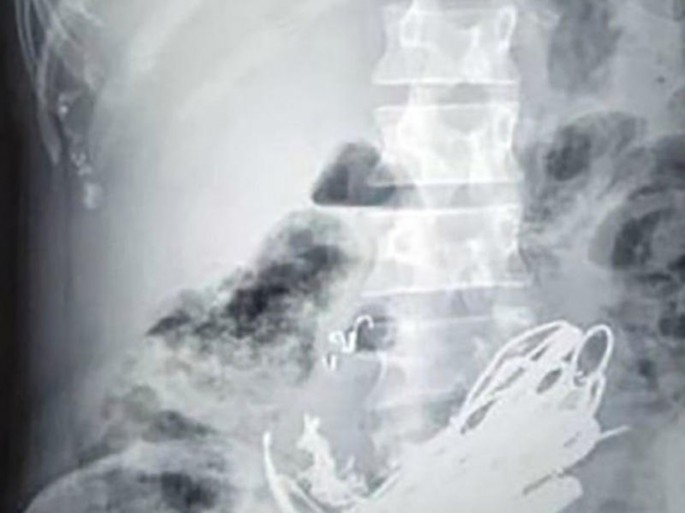

Hindistanda bir qadın həkimləri mat qoyub. Avtosfer.az sputnik.az-a istinadən xəbər verir ki, həkimlər onun mədəsində yarım kiloya yaxın həzm olmayan əşyalar aşkarlayıblar. Bunların içində qoz qabığı, dəmir bolt və digər əşyalar olub. Sangita adlı qadın mədəsində kəskin ağrı olduğu üçün həkimə müraciət edib. Nitin Parmar adlı həkim xəstəni müayinə edən zaman qeyri-adi halla qarşılaşıb. 40 yaşlarında olan qadın rentgenlə müayinə edilən zaman qarnında mis üzük, saç sancağı, dəmir bolt, qoz qabığı və digər əşyalar aşkarlanıb. Həkim xəstəni dərhal əməliyyat edib. Hazırda xəstənin vəziyyəti normaldır. Həkimlər iddia edir ki, qadın çox az rast gəlinən psixoloji xəstəlikdən əziyyət çəkir. O, qeyri-ixtiyari olaraq həzm olmayan və insan sağlamlığı üçün təhlükəli əşyaları udur.